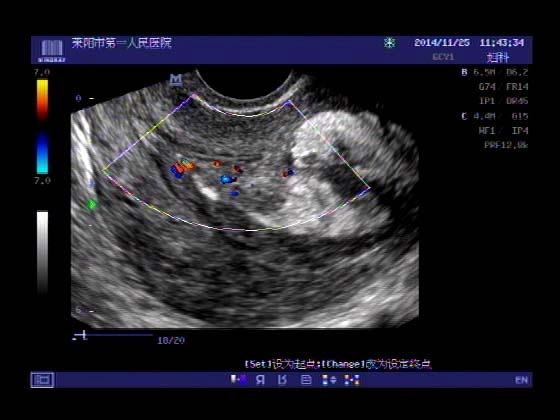

超声入门贴379---------粘膜下肌瘤(阴超的魅力)

女,43岁,月经量多3个多月,加重一个月

外院彩超检查提示:子宫后肌壁略高回声团------肌瘤?息肉?,盆腔少量积液

今天来我院检查:

巧妇难为无米之炊,经腹部超声确实很难定,阴超一目了然,乡镇医院诊断水平的提高更迫切的需要高档仪器的引进!